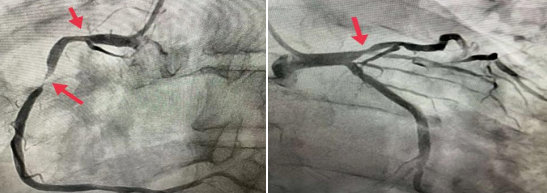

今年53歲的王大爺,冠狀動脈造影結果提示右冠狀動脈中段狹窄99%,右冠近端及前降支近端狹窄在70%左右,處于臨界病變,要不要都植入支架呢?

馬登峰對王大爺狹窄的血管進行FFR檢測,將一根壓力微導管送入狹窄血管的遠端,通過連接的儀器進行測試,右冠近端與前降支近端測試FFR值分別為0.91和0.85,均提示不需要植入支架治療,只需要在右冠中段狹窄99%處植入一枚支架。